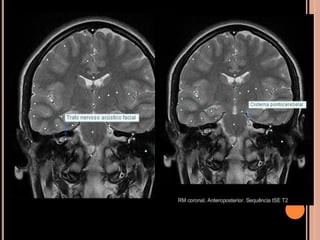

NF1 - RM

Gliomas de via óptica:

Espessamento da bainha/nervo de aspecto

tubular/fusiforme ou globular

Hipossinal em T1 e hipersinal em T2

Impregnação homogênea pelo Gd;

Ocasionalmente dilatação do espaço subaracnoideo

perineural;

Pode haver extensão ao quiasma óptico e aos corpos

geniculados laterais;

Gliomas do tronco encefálico:

Maioria benigno, podendo estabilizar-se ou regredir

Isossinal em T1 e hipersinal em T2;